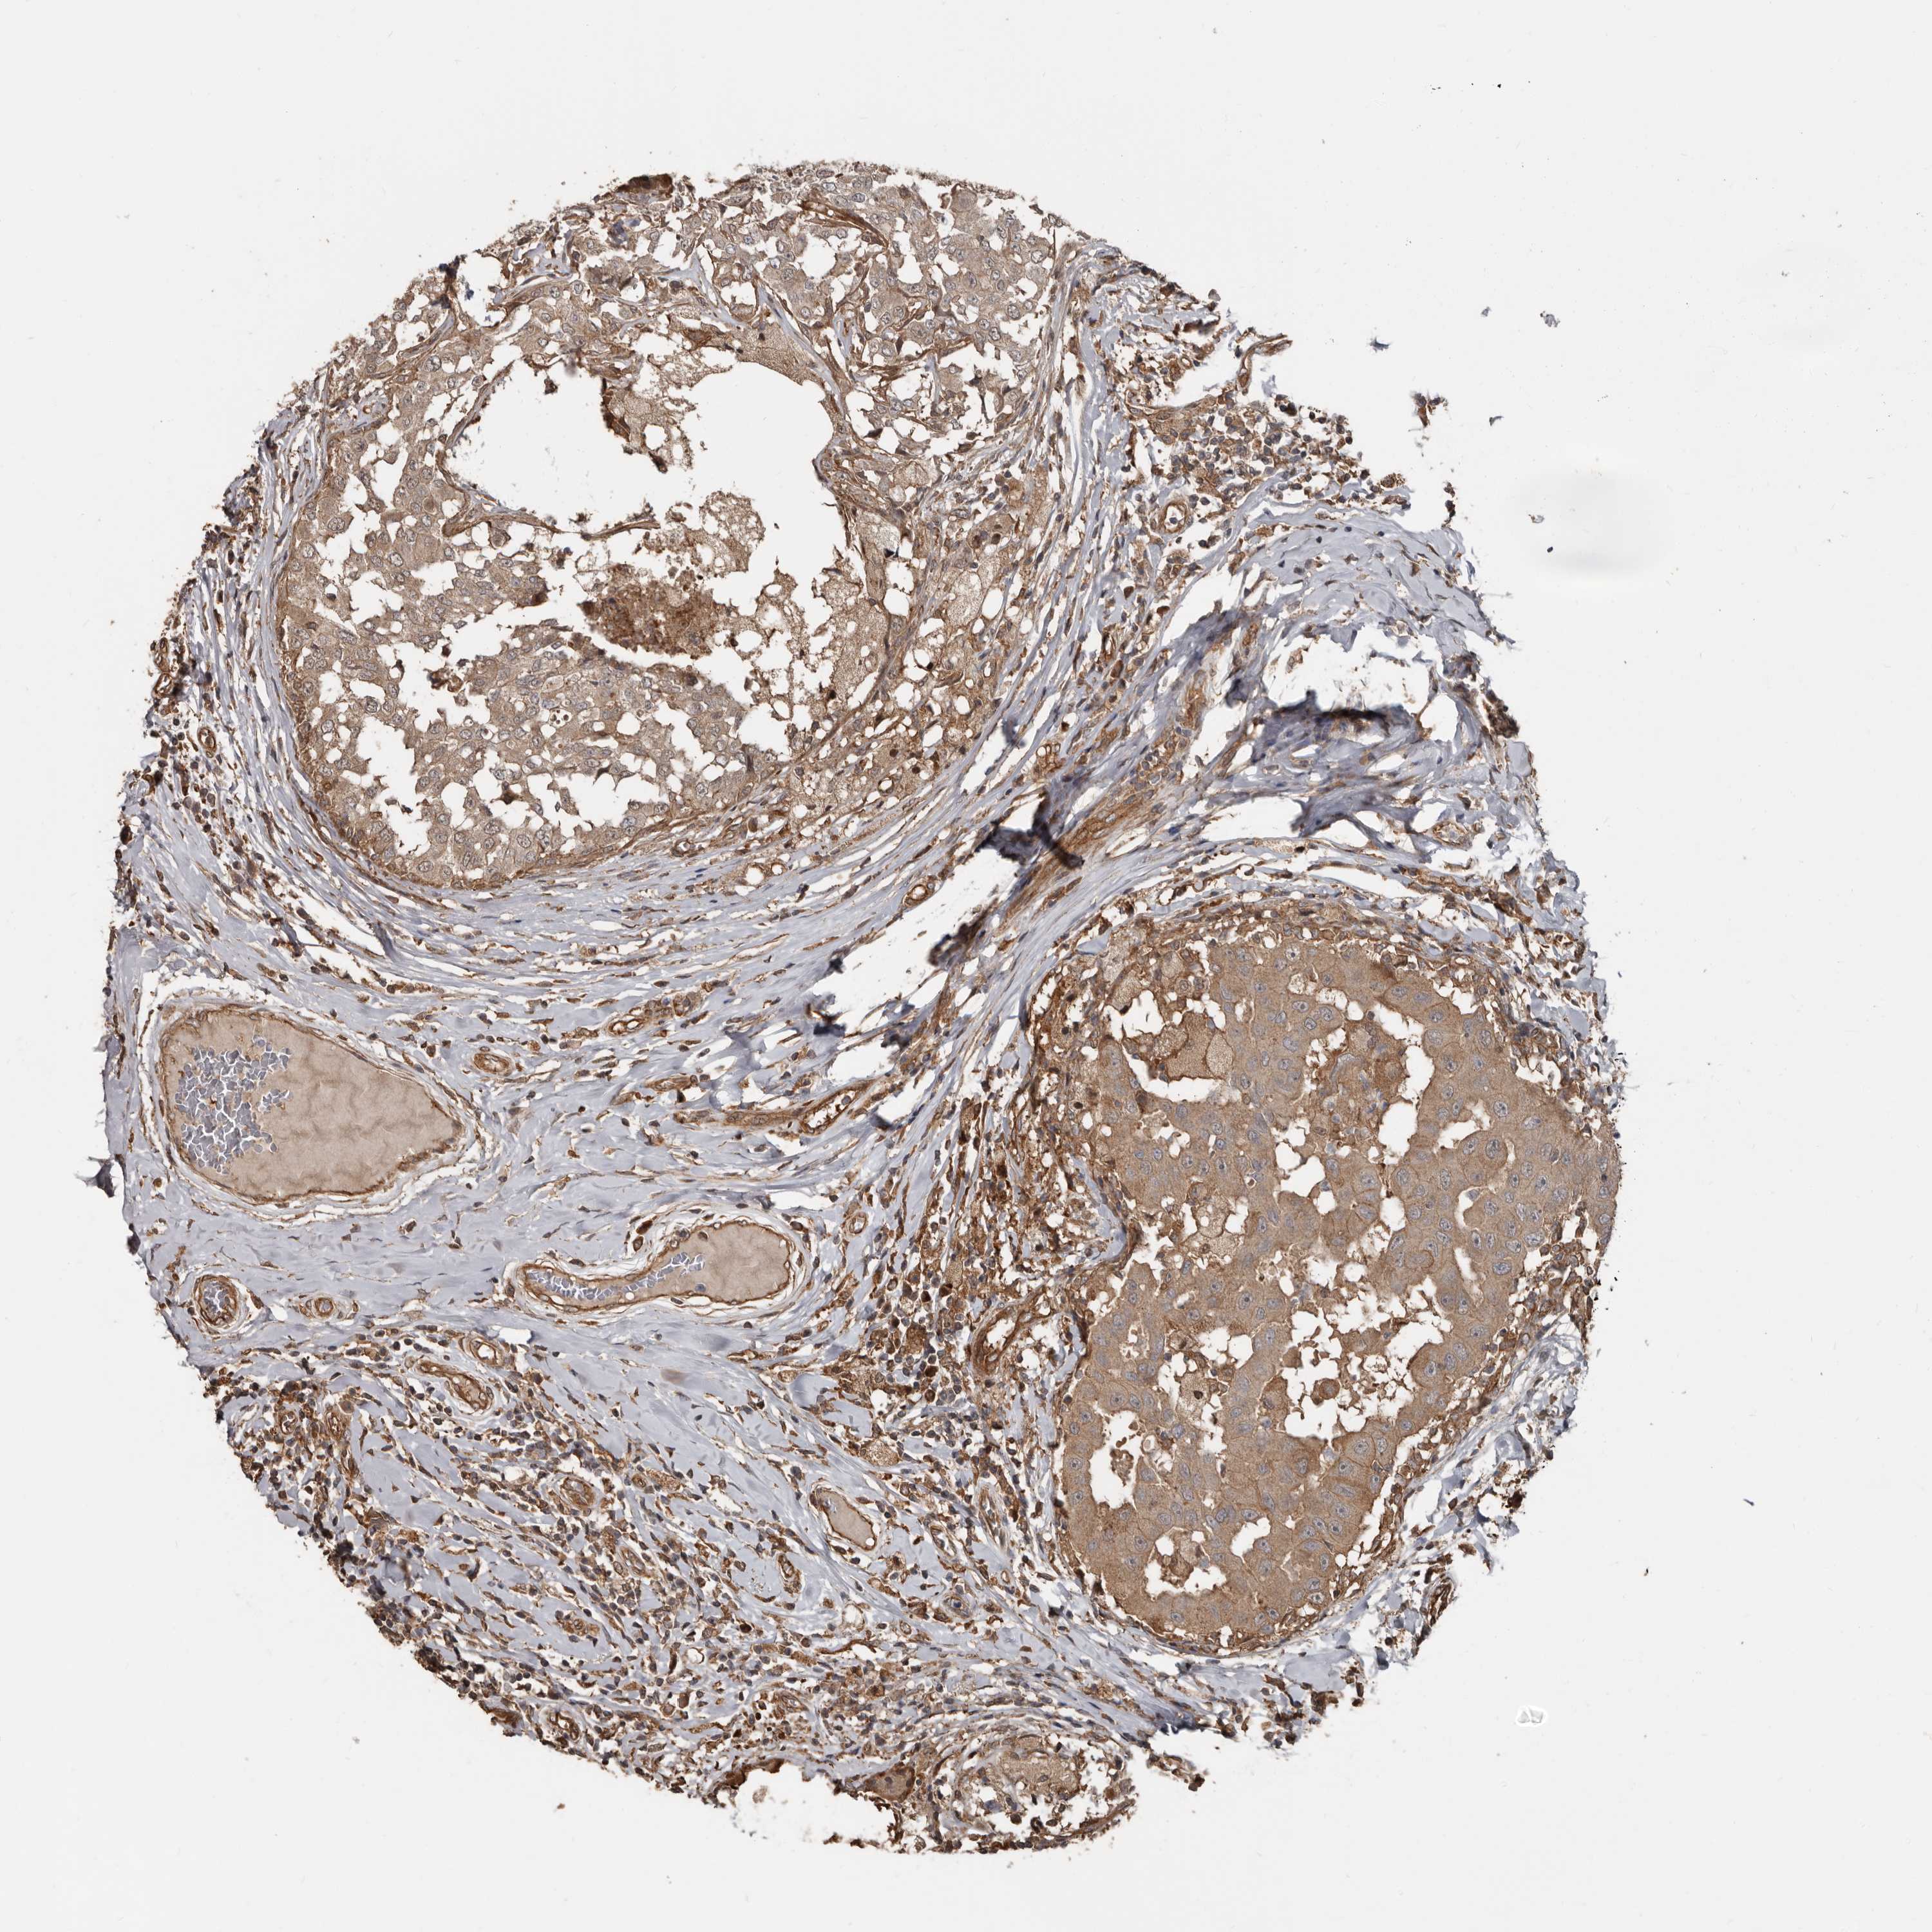

CANCER BREAST CANCER Show tissue menu

BRCA TCGA BRCA VALIDATION PROTEIN EXPRESSION